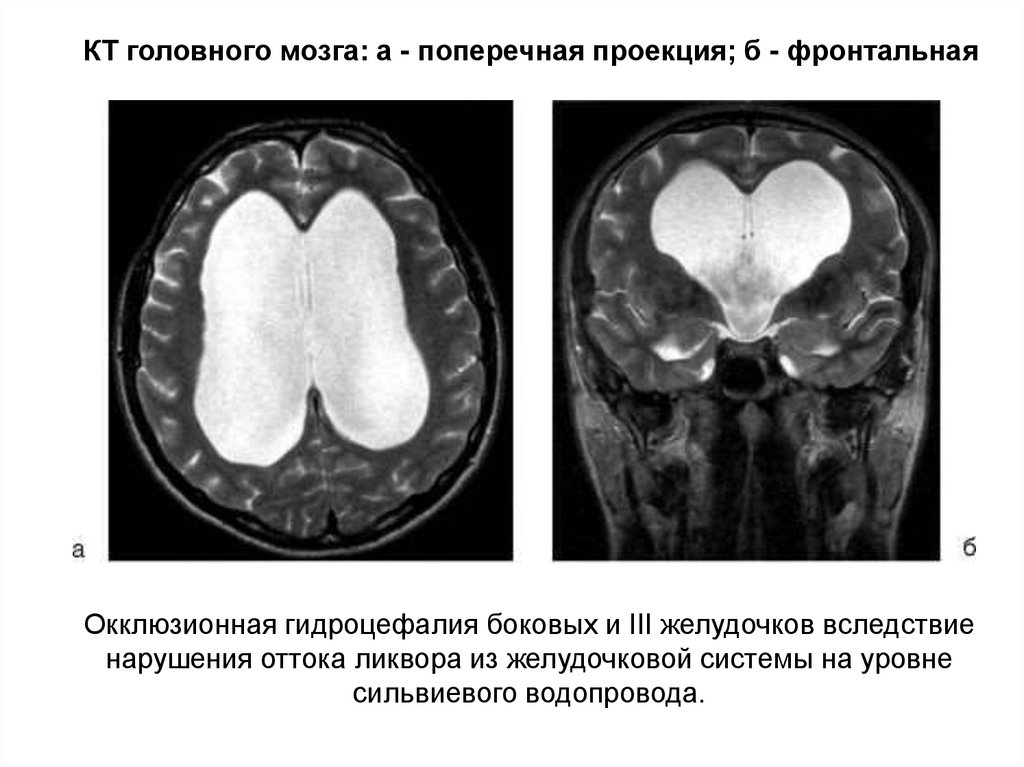

Признаки умеренно выраженной наружная

Признаки умеренно выраженной наружная 113 фото